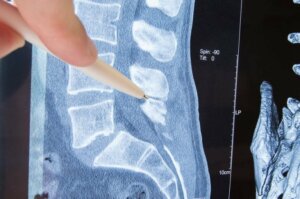

Ce este radiculopatia? Ca să înțelegi mai bine ce presupune această afecțiune, trebuie să reții câteva informații de bază despre coloana vertebrală.

Coloana vertebrală reprezintă o structură osoasă alcătuită din vertebre care, la rândul lor, protejează oasele și permit mișcarea. Vertebrele prezintă găuri de o parte și de alta, prin care ies nervi ce pornesc din diverse părți ale corpului.

Componentele nervilor care ies prin vertebre se numesc rădăcini nervoase. Radiculopatia presupune o comprimare a nervilor la nivelul rădăcinilor. Care sunt cauzele și manifestările clinice ale acestei afecțiuni? În cele ce urmează, vom oferi răspunsuri la aceste întrebări și îți vom prezenta opțiunile de tratament disponibile.